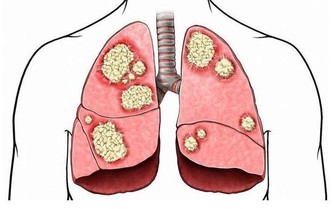

2.4 減少癌症風險

部分研究指出,定期捐血與降低某些癌症(如肝癌與肺癌)風險之間存在一定關聯,特別是體內鐵含量偏高者。